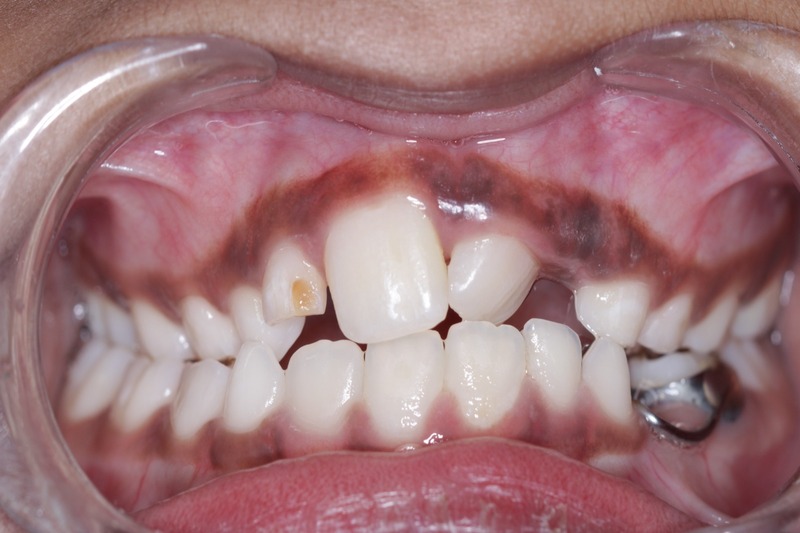

Early braces treatment correct the irregularly placed teeth and create room for erupting permanent teeth. correct bite problems such as open bite, cross bite and improves the appearance and self esteem of the child.